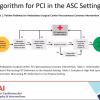

May 15, 2020 – The Society for Cardiovascular Angiography and Interventions (SCAI) issued a position statement on the…